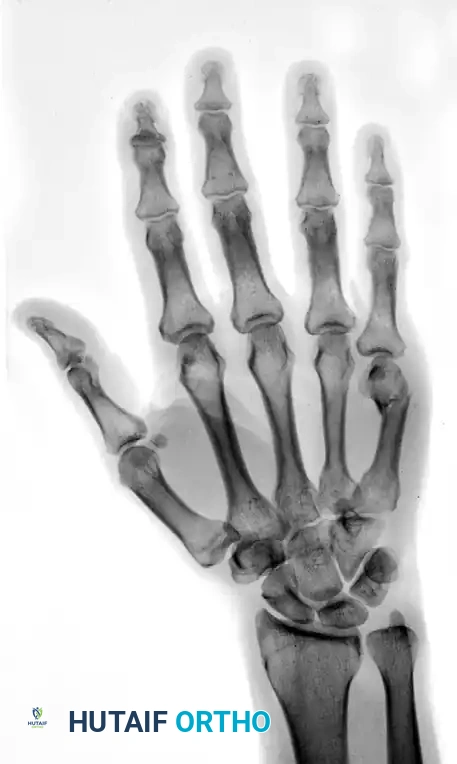

Review the preoperative deformity carefully to understand the required reduction vectors.

FIGURE 67-35A: Preoperative AP radiograph of a fifth metacarpal neck fracture.

FIGURE 67-37A: Preoperative AP radiograph of a fourth metacarpal shaft fracture.